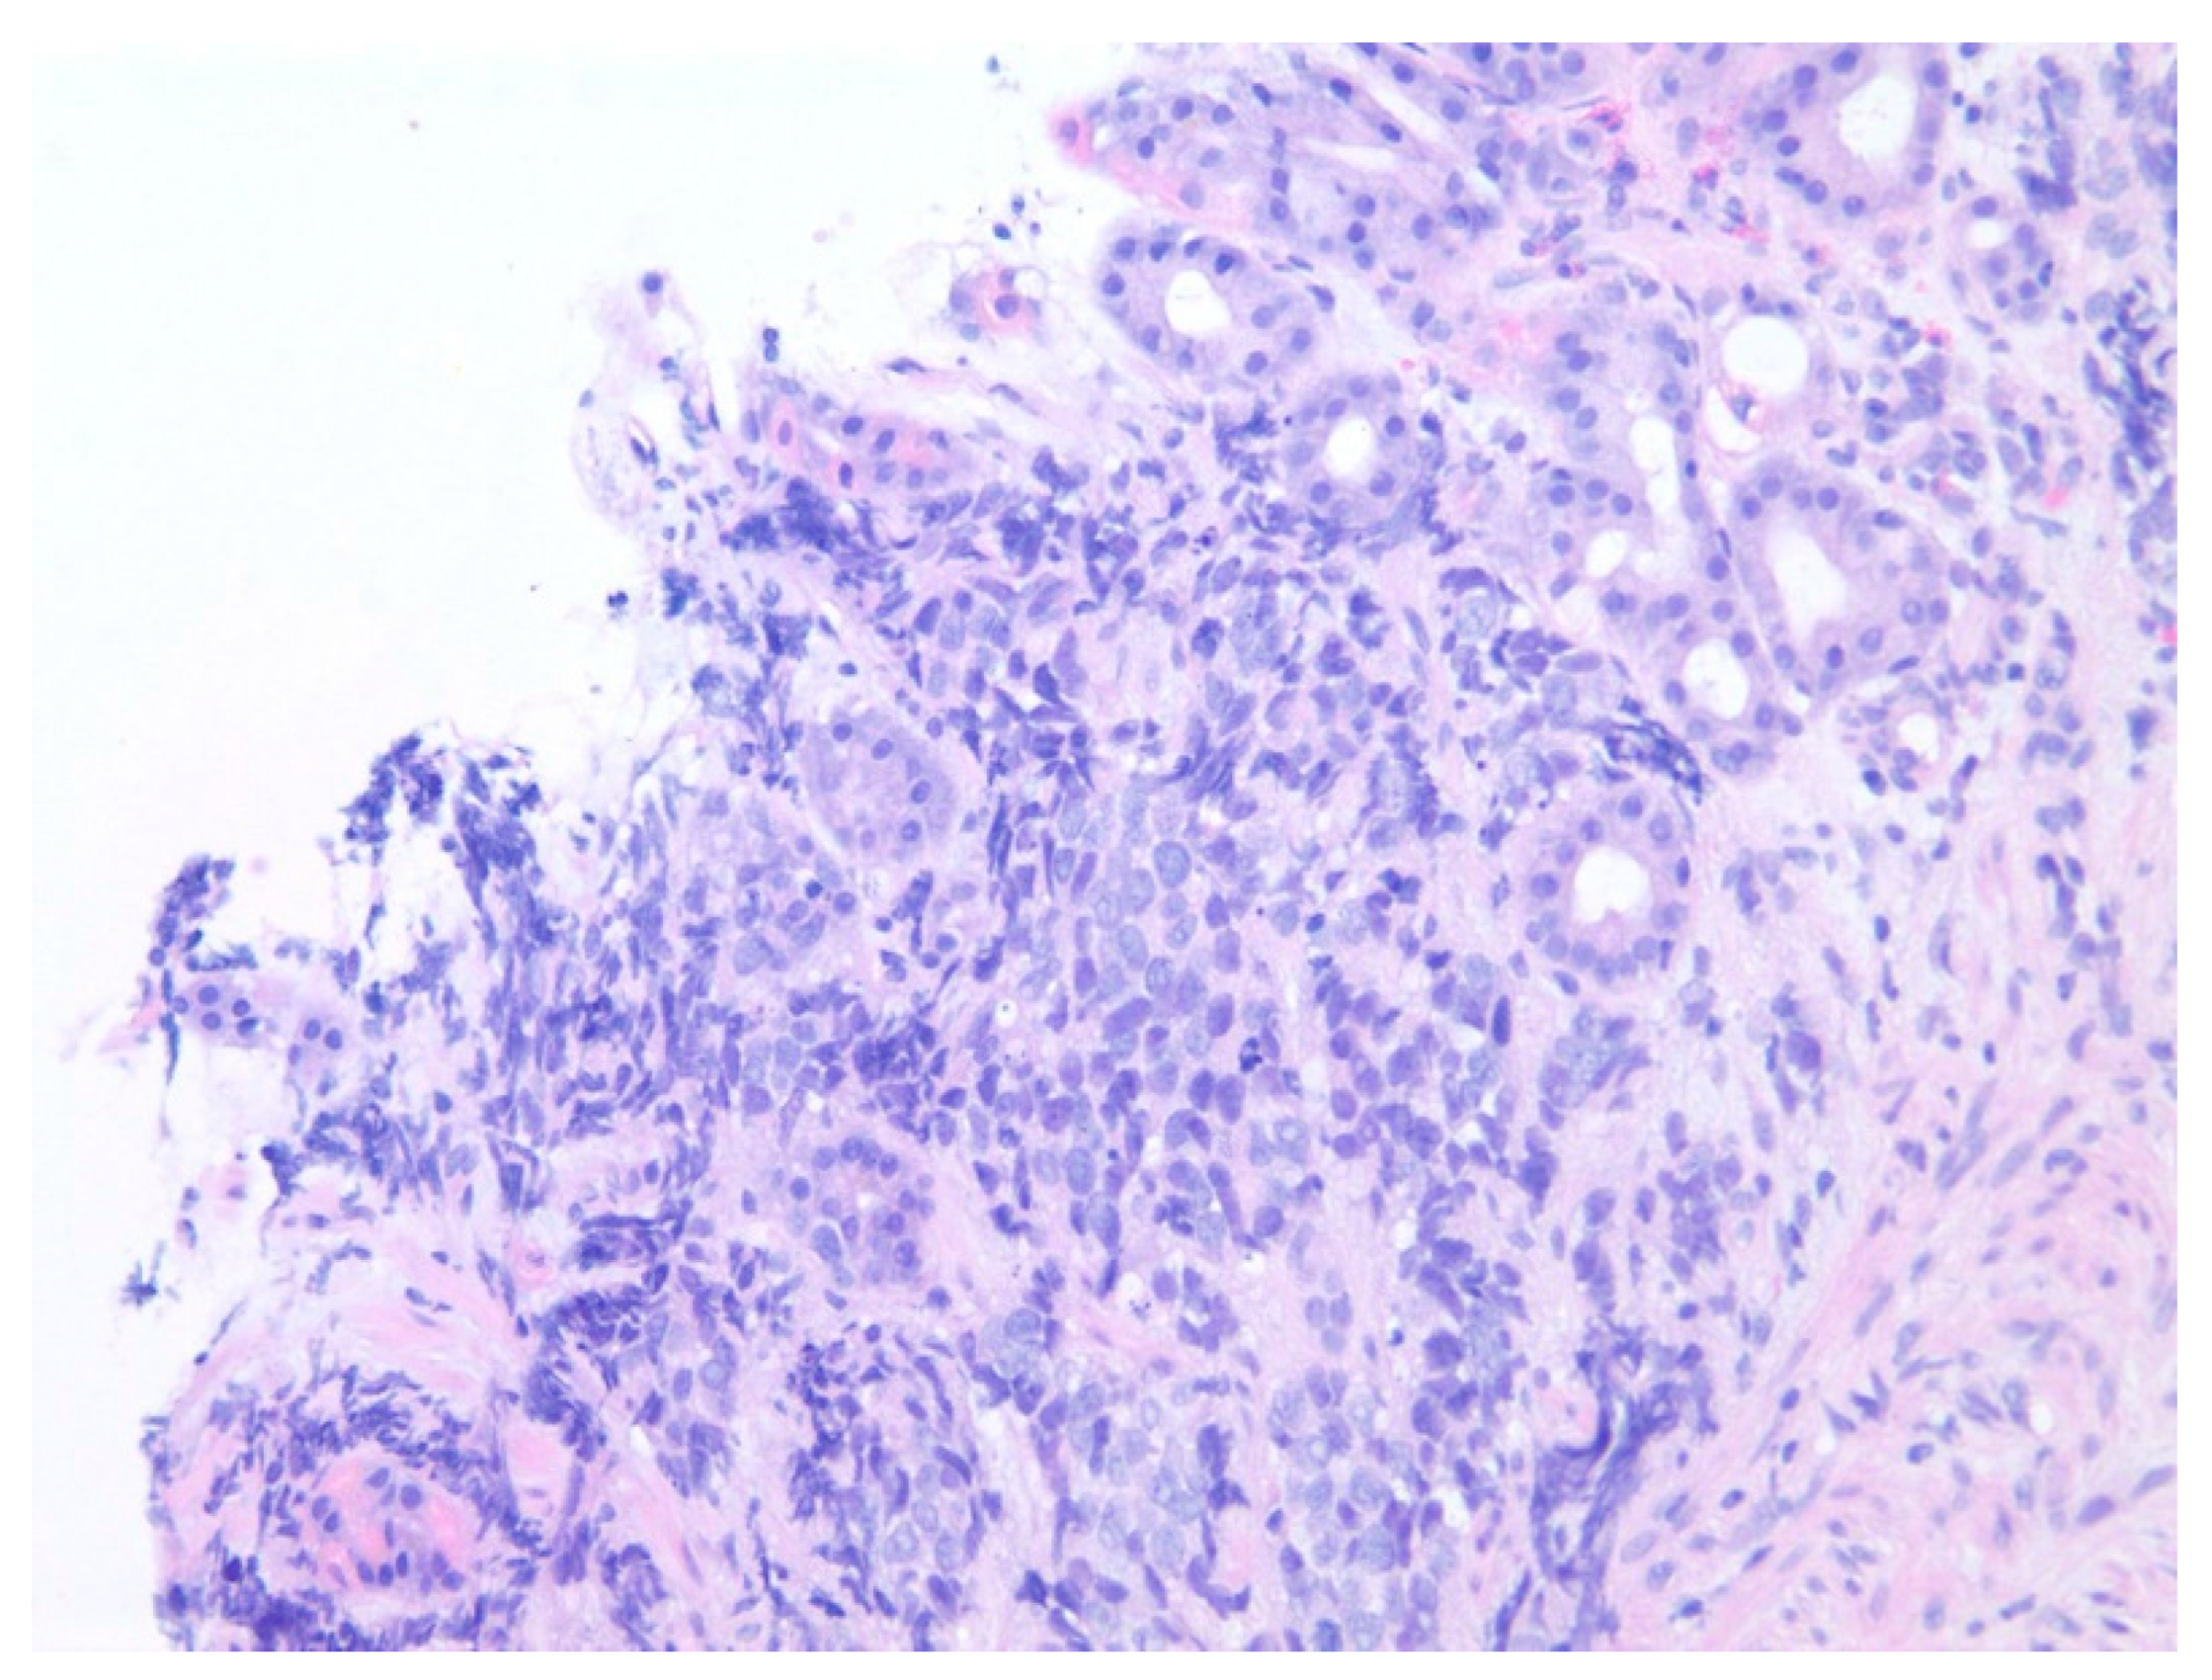

| 1 | F | 66 | Skin | Fundus, cardia, and body | Polypoid lesions with superficial ulcers | Esophagus, duodenum, mediastinum, cervical soft tissue, pancreas | Metastatic malignant melanoma | Radiotherapy and immunotherapy | Comfort care and death 5 days after EGD diagnosis of metastasis |

| 2 | M | 84 | Lymphoid | Fundus and cardia | Ulcerated and necrotic mass | Liver, urinary bladder | Diffuse large B-cell lymphoma | None | Death in 2 months after EGD diagnosis of metastasis |

| 3 | F | 35 | Lung | Fundus | Fungating mass | Esophagus, mediastinum | Large-cell neuroendocrine carcinoma | Chemotherapy-carboplatin/ etoposide | Death 1 month after EGD diagnosis of metastasis |

| 4 | F | 73 | Kidney | Fundus and body | Multiple large friable masses | Liver and lungs | Clear cell renal carcinoma | Nephrectomy, chemotherapy, immunotherapy (Axitinib) | Death 10 days after EGD diagnosis of metastasis |

| 5 | M | 76 | Lung | Body | Cratered ulcers | Liver, bone and adrenals | Small cell carcinoma (poorly differentiated neuroendocrine Ca) | None | Death 7 days after EGD diagnosis of metastasis |

| 6 | M | 61 | Lymphoid | Unknown | Clean based ulcer | None | Marginal zone lymphoma | Rituximab, Zanubrutinib, umbrasilib. OCHOP regimen currently | Progressive disease per latest scans despite therapy |